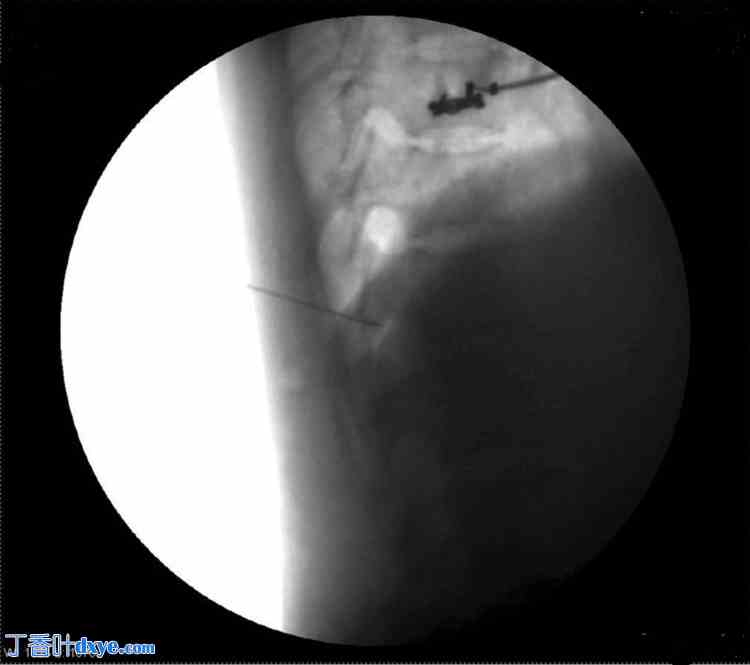

患者取俯卧位。涂抹并铺巾后,在C臂辅助下将T8横突定位于右侧。在透视引导下插入Quincke针(22 G),到达T8横突。针尖沿横突向尾部推进,直至感觉无阻力。在透视下注射碘海醇300放射性造影剂确认针头位置,并拍摄前后位和侧位图像(图1-4)。

图3. 针头位于T12侧位。